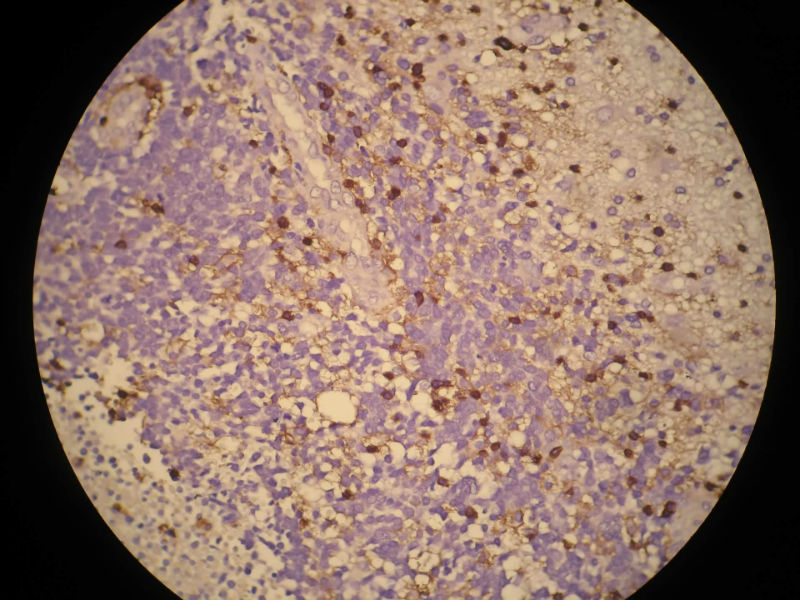

患者,M50Y,左侧肢体乏力半个月,肌力2级

MRI示右顶叶和小脑占位性病变,增强强化明显

Based on histology and immunohistochemistry, metastatic neuroendocrine carcinoma needs to be ruled out. I suggest TTF-1 stain. Also pay attention to nuclear morphology at high power view and see if it fits small cell carcinoma. It doesn't have to be a primary CNS tumor just because the border appears infiltrative.

谢谢Dr.mjma和楼上各位的指导。形态学符合小细胞癌。我们加做TTF-1,CD56和NSE,下周有结果。